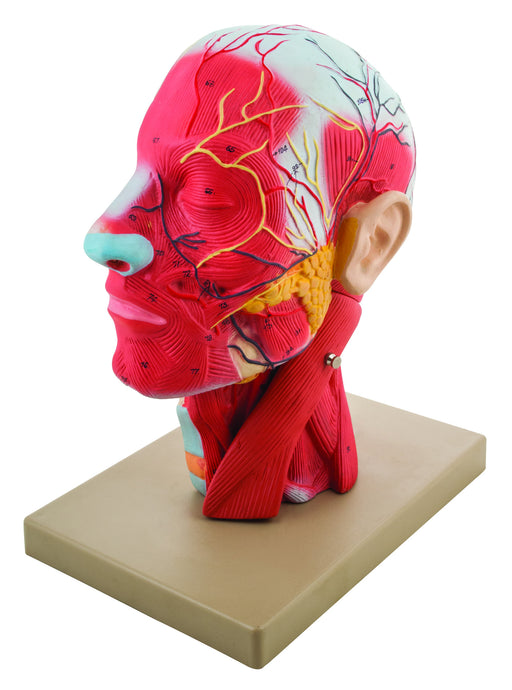

Model, Human Head, Cross sectional, Neck, Life Size, Cranium

The model comprehensively showcases the human head and neck muscles, vessels, nerves and internal structures Life sized The life-size human head a...

View full detailsAM25AS -